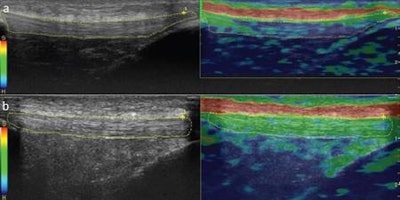

Sonograms and color-coded images of the patellar tendon of a smoker (A) and a nonsmoker (B). The smoker's patellar tendon has a grade 1 (hardest tissue) blue color code, while the nonsmoker's tendon has a grade 3 (intermediate tissue) green color code. Images courtesy of the Journal of Ultrasound in Medicine.In other results, the researchers found weak negative correlations between the smoking amount and patellar tendon thicknesses, as well as strain ratio measurements pertaining to the patellar tendon and the proximal third of the Achilles tendon, Akkaya said.